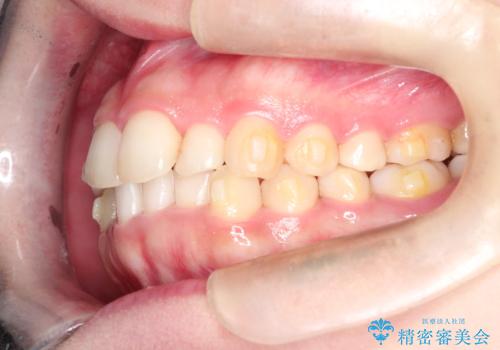

インビザラインでの前歯のガタガタの矯正

- 上下の前歯のがたつきを主訴に来院されました。

歯と歯の間をわずかに削りスペースを作り、インビザラインにて矯正治療を行うこととしました。

使用時間を守っていただけたので、スムーズに矯正を終了することができました。